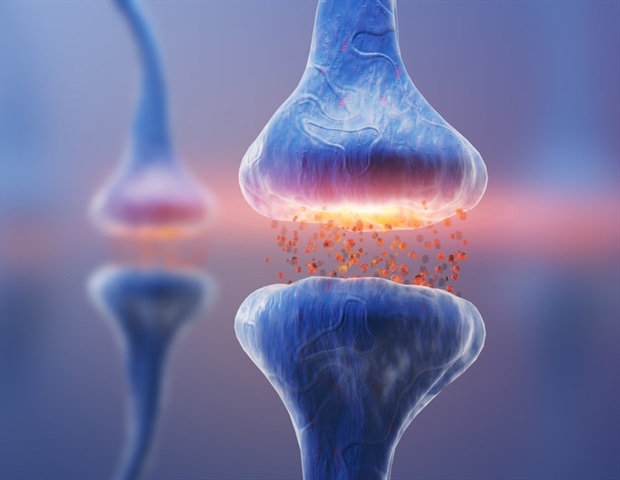

Investigational anti-clotting drug reduces risk of second ischemic stroke without bleeding concerns

Health

Really Simple SyndicationFebruary 7, 2026

An investigational anti-clotting medication, asundexian, demonstrated a reduction in the risk of a second ischemic (clot-caused) stroke without raising bleeding concerns, according to a preliminary